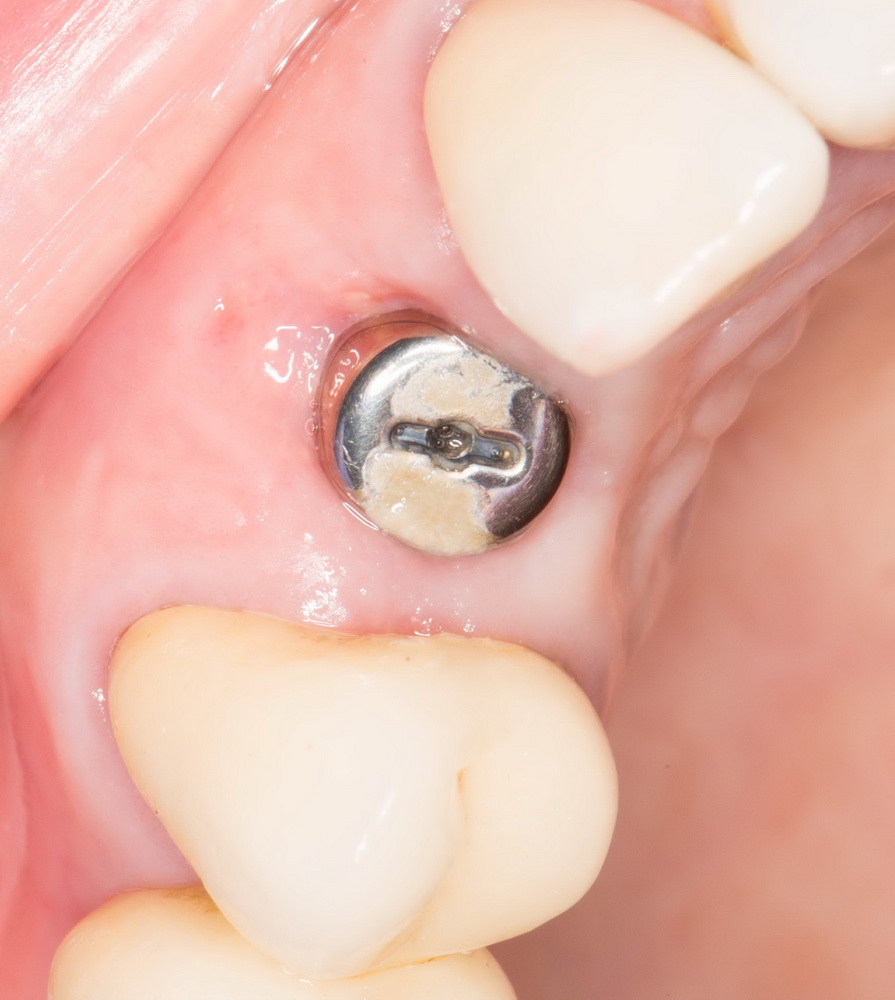

На имплантат устанавливаем формирователь десны. В тот момент я думал, что ставим его временно, так как после операции в планах была коронка на имплантат:

Мы планируем восполнение отсутствующей передней стенки лунки с помощью биоматериалов, и именно для этого нужен формирователь десны. Чтобы в шахту импланта не натолкать лишнего.

Итак, накладывается Mucograft Seal. Также успешно можно использовать любую коллагеновую матрицу любого размера:

Он подшивается узловыми швами. Операция закончена. Вид послеоперационной раны:

или вот: